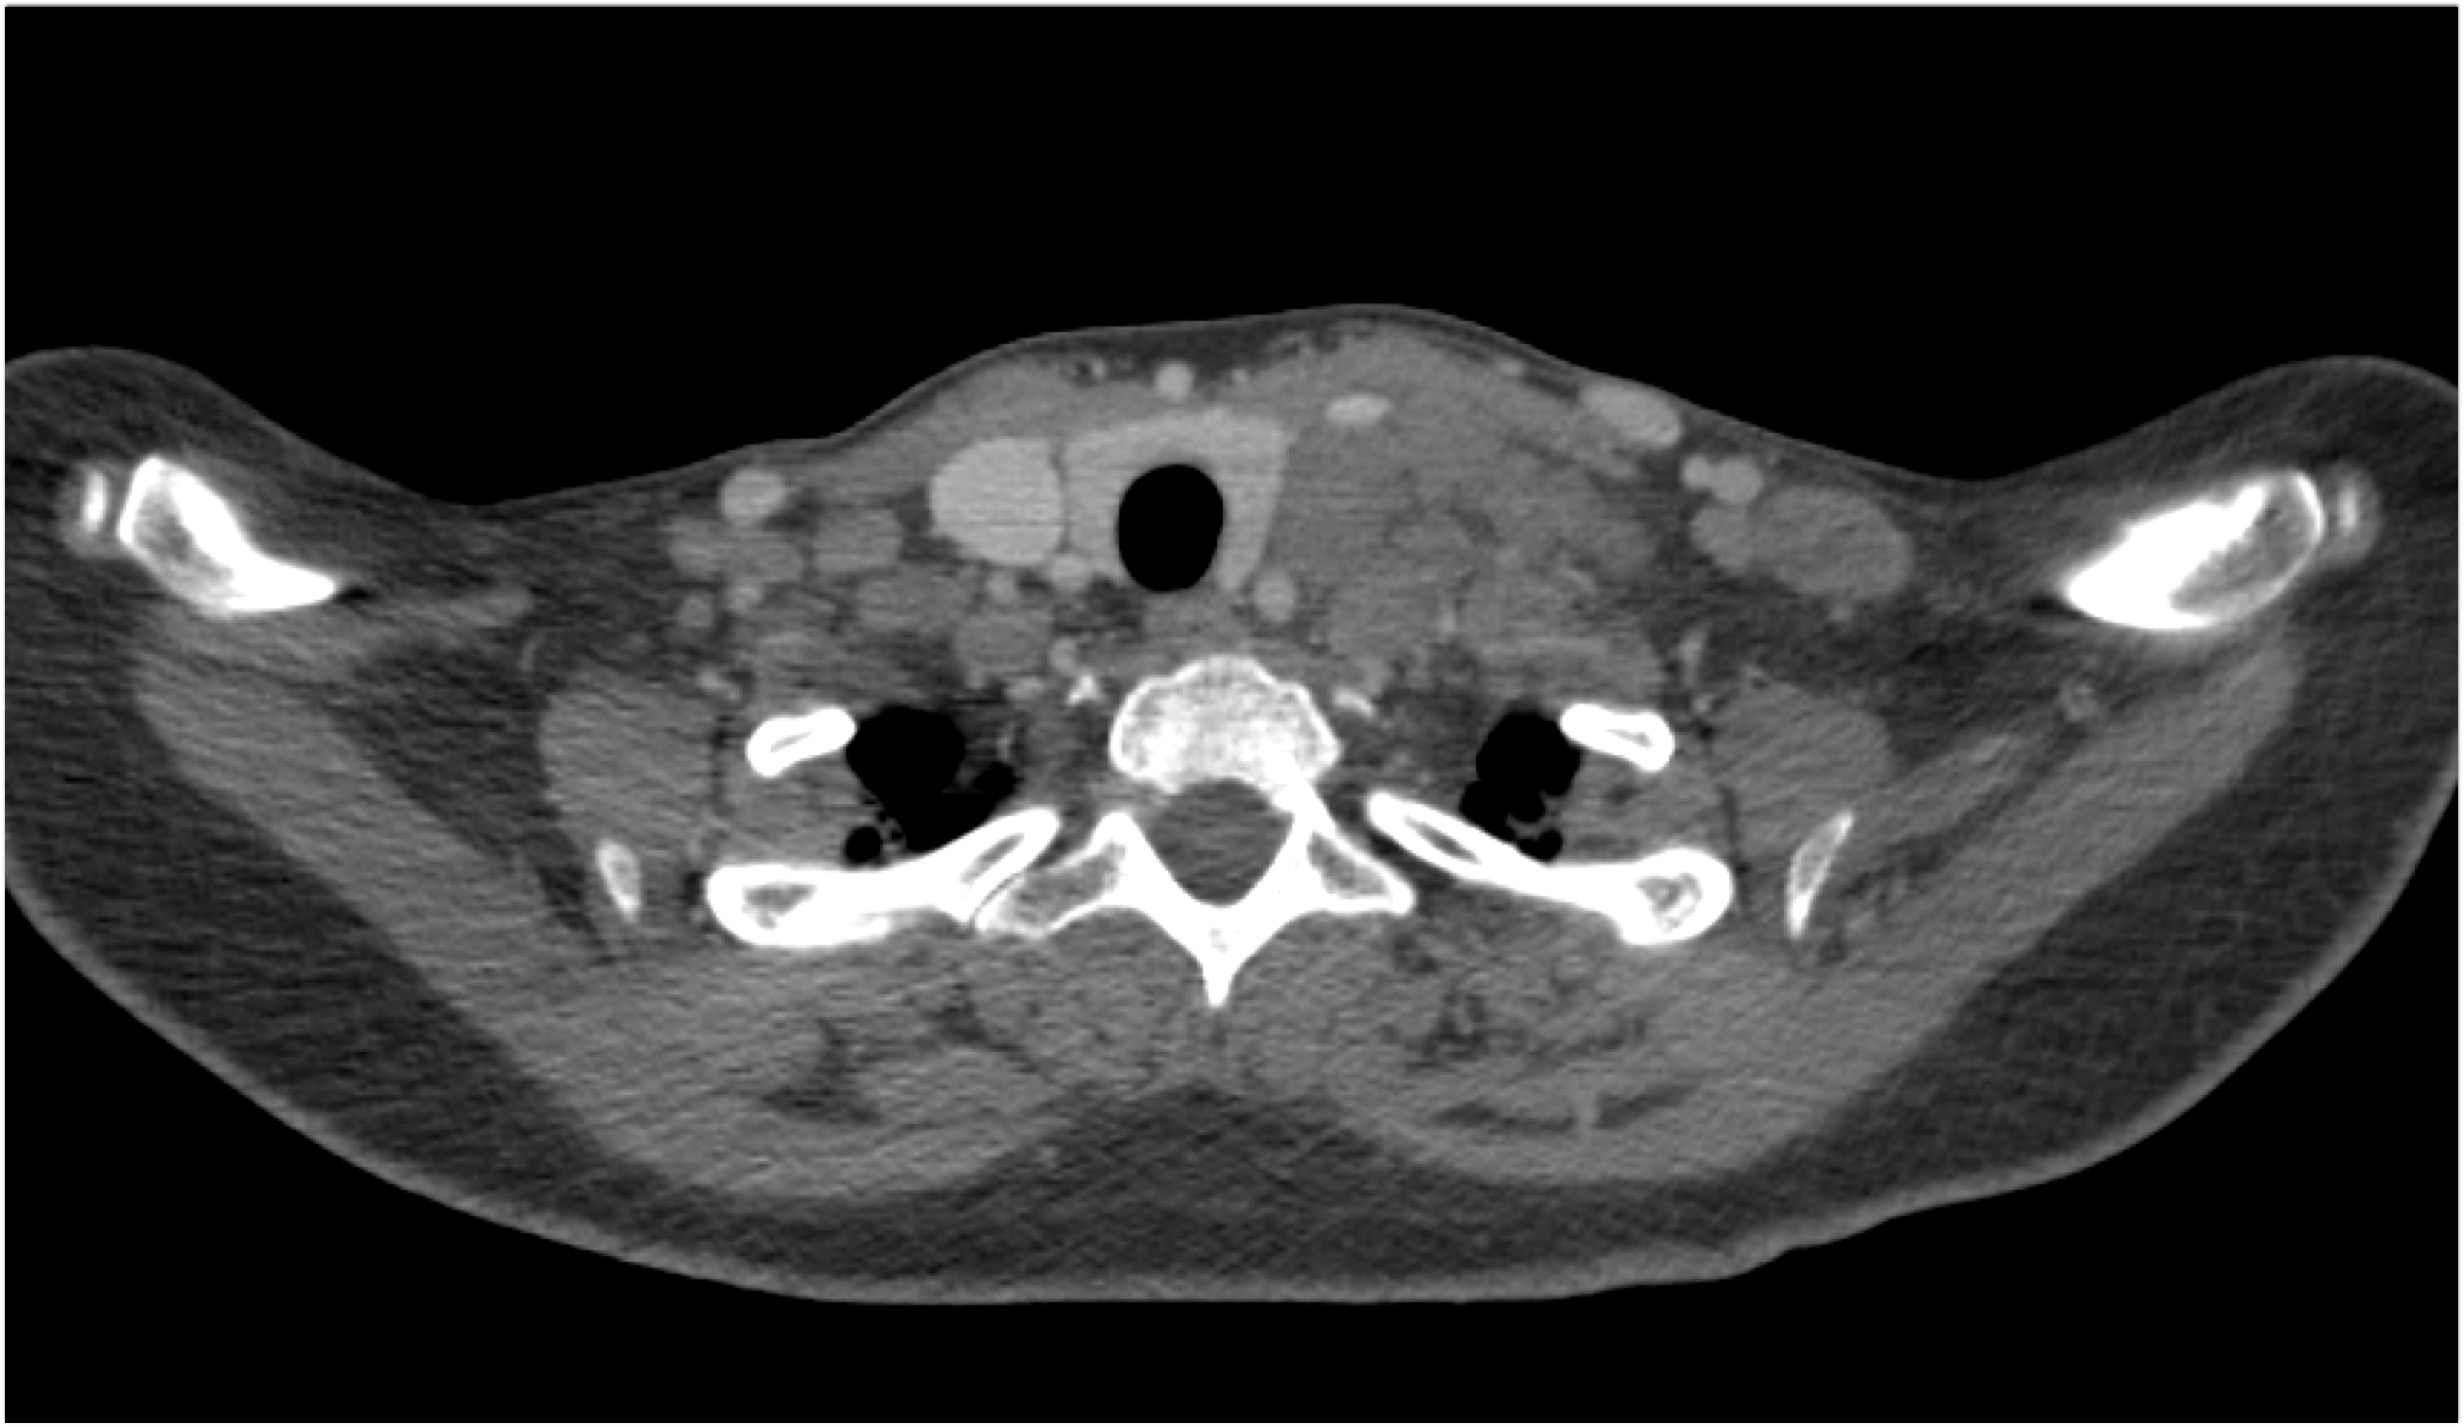

8) In this patient with mediastinal widening on CXR the best diagnosis is?

lymphoma

germ cell tumor

lung cancer

teratoma